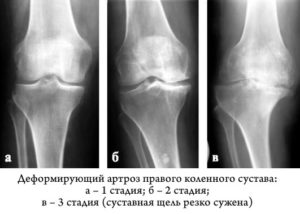

- 1 степень практически незаметна, начальные признаки отсутствуют, а все деформирующие изменения протекают медленно;

- 2 степень сопровождается появлением легких дискомфортных состояний, снижением подвижности сочленения, иногда – быстрой утомляемостью и легкой болезненностью при усиленных нагрузках;

- 3 степень проявляется явными изменениями в структуре хряща, что визуально сопровождается изменением формы и величины сустава, ощутимой утратой подвижности, снижем работоспособности и сильной острой болью;

- 4 степень – последняя фаза, при которой подвижность сочленения практически отсутствует, боли усиливаются даже в спокойном состоянии, а затем прекращаются.

При третьей и четвертой степени деформирующего артроза отчетливо слышны хрустящие звуки, заметно покраснение кожи в области пораженного сустава.